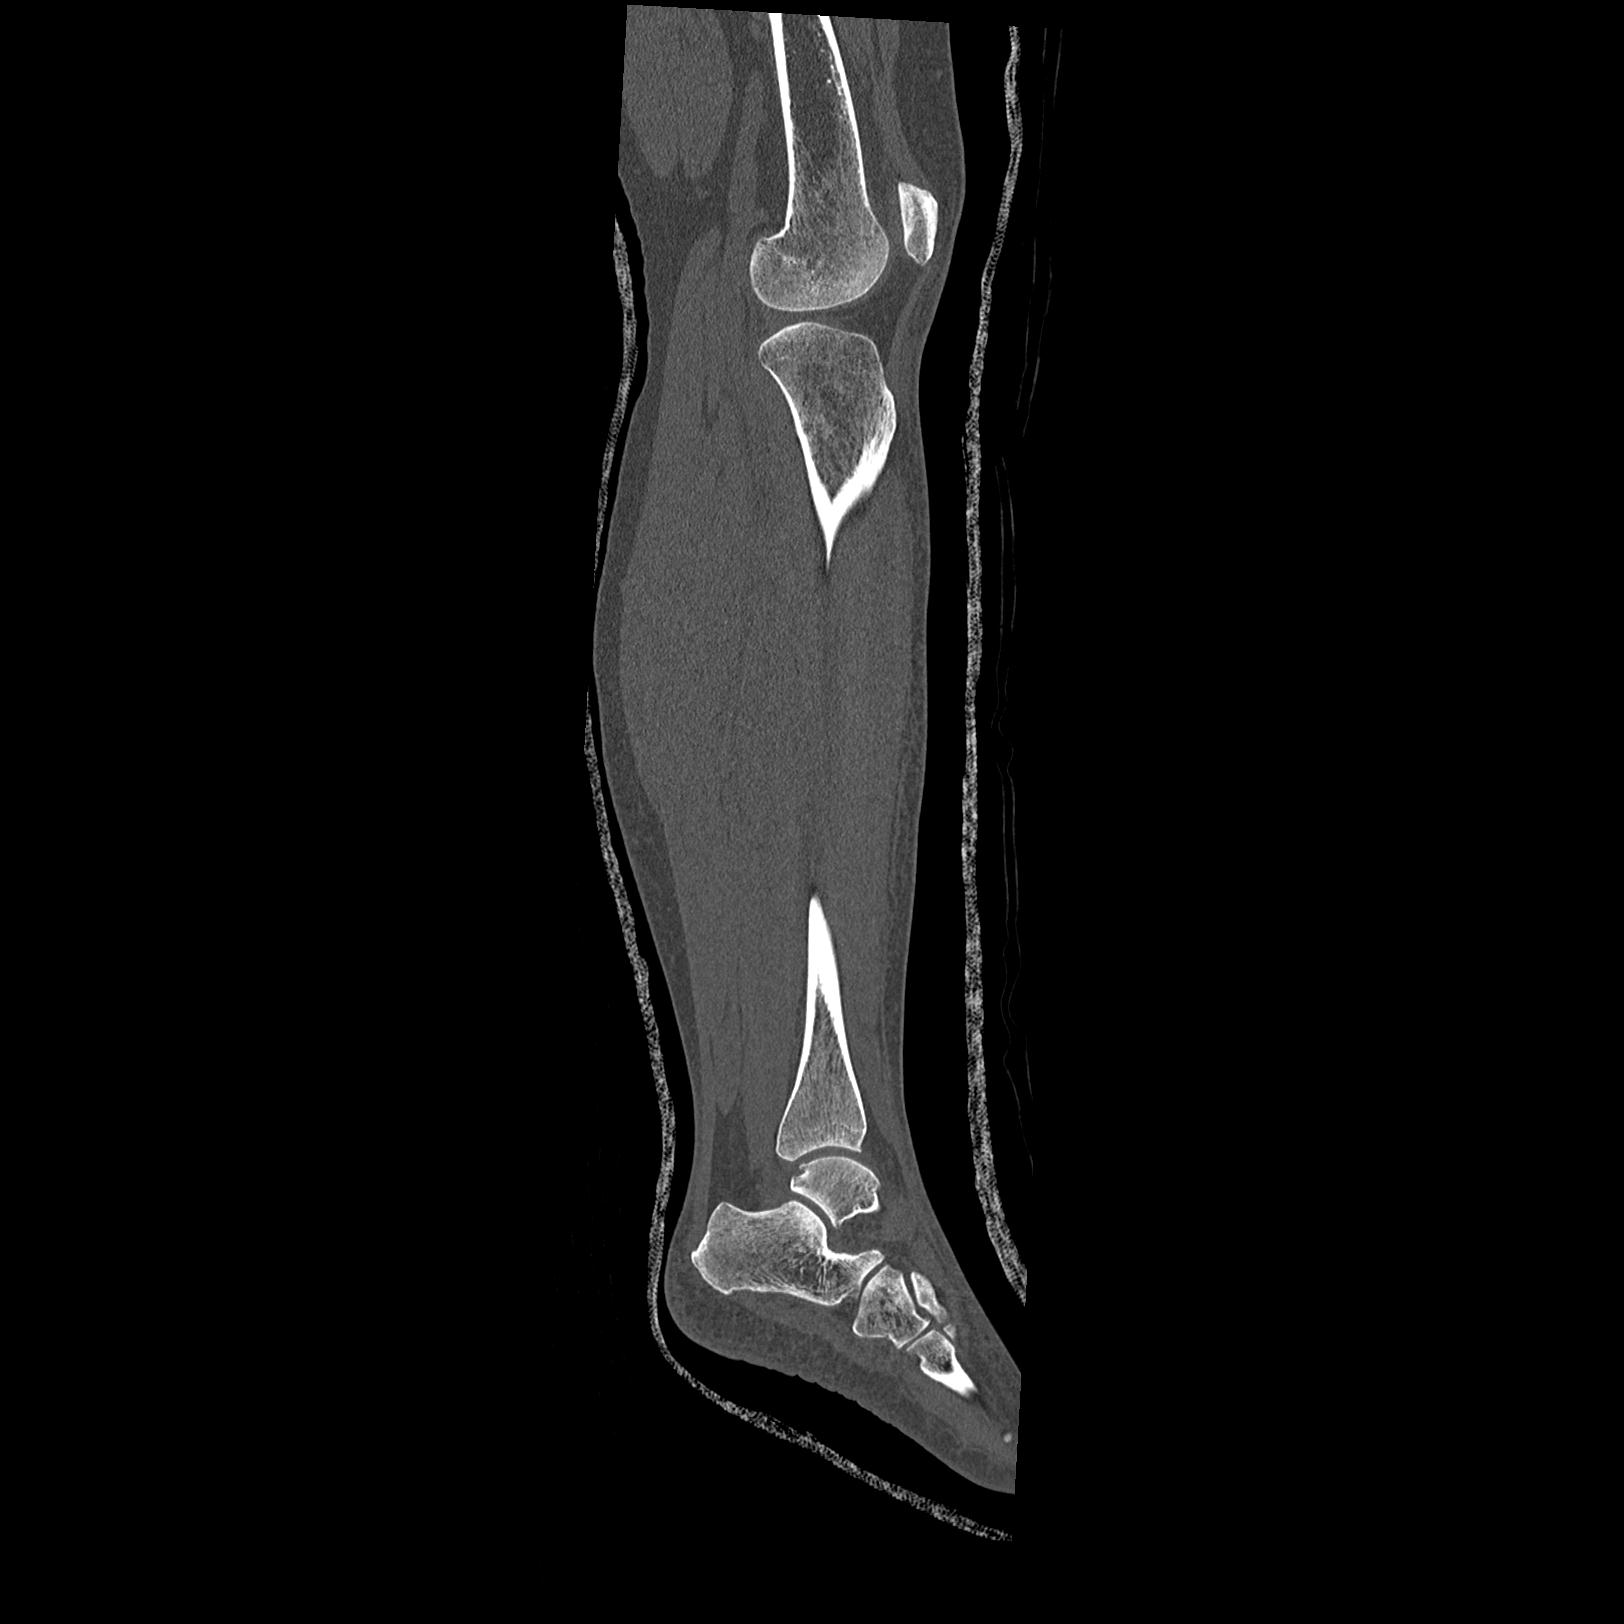

102803 1/12(キウスなし) 1/27 左下腿 4R 30歳女性 左脛骨軸内釘